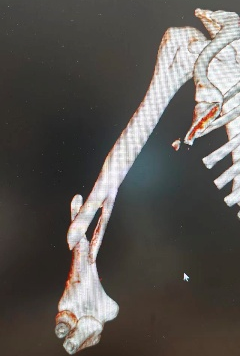

10月3日,60岁的陆女士(化名)滑倒后右手撑地,16:30入院就诊,顾晓娟医师团队诊断为:右尺桡骨骨折,充分评估后,22:00开始手术,1小时后返回病房。

图片